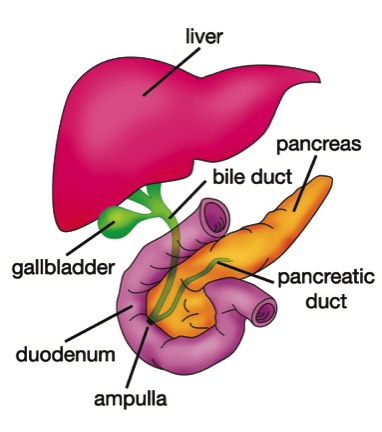

What is the gall bladder and what does it do?The gall bladder is a small bag, roughly the shape and size of a pear, that sits underneath the liver, on the right side of the abdomen.

The liver makes bile. The bile flows out of the liver through a tube that is called the common bile duct. This emerges from the under surface of the liver, and is roughly the thickness of a drinking straw. The gall bladder hangs off the bile duct at this point, just after it has emerged from the liver, a bit like a pear hanging from a branch. The bile duct then runs downward and enters the duodenum (a part of the intestine) where the bile mixes with the food. The pancreatic duct, which drains the digestive juice from the pancreas, also empties into the intestine at the same place.

The gall bladder stores some of the bile that is produced by the liver. After a meal, especially a fatty meal, chemical signals go to the gall bladder, which then squeezes out the bile it has stored, into the bile duct, and from there into the gut.